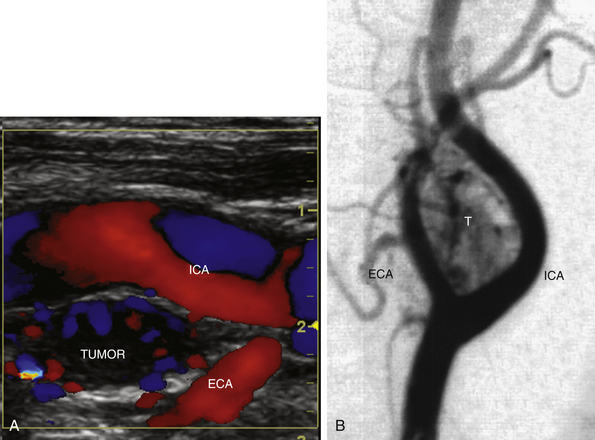

РИСУНОК 10-10. Опухоль каротидного тела. А. На этом продольном цветном изображении видна гомогенная гипоэхогенная опухоль ( ОПУХОЛЬ ), которая расширяет ветви внутренней сонной артерии (ВСА) и наружной сонной артерии (ЕСА). Кровоток (цветные участки) легко обнаруживался в опухоли. Б. Каротидная артериография в боковой проекции показывает высоковаскулярный характер образования ( Т ).